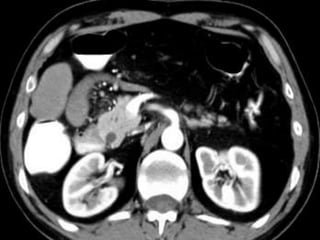

61 years old man with epigastric pain and vomiting

young patients (20–40 y), F : M  CT angiograms:            focal narrowing in the proximal celiac axis.             inspiration and expiration          2ry signs poststenotic dilatation and collaterals.ttt   : surgery.

angulations and narrowing of the proximal celiac axis. Sagittal 3D image of a patient with epigastric pain

Sagittal (MIP) of a patient with recurrent abdominal pain reveals focal calcified plaque.